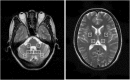

Background: Spinocerebellar ataxia type 3/Machado-Joseph disease (SCA3/MJD) is one of the nine polyglutamine (polyQ) diseases and is caused by a CAG repeat expansion within the coding sequence of the ATXN3 gene. Few multimodal imaging analyses of the macro- and micro-structural changes have been performed. Methods: In the present study, we recruited 31 genetically-confirmed symptomatic SCA3/MJD patients and 31 healthy subjects as controls for a multimodal neuroimaging study using structural magnetic resonance imaging (sMRI), proton magnetic resonance spectroscopy (1H-MRS) and diffusion tensor imaging (DTI). Results: The SCA3/MJD patients displayed a significantly reduced of gray matter volume in the cerebellum, pons, midbrain and medulla, as well as inferior frontal gyrus and insula, and left superior frontal gyrus. The total International Cooperative Ataxia Rating Scale (ICARS) score was inversely correlated with the gray matter volume in the cerebellar culmen, pons and midbrain. The numbers of CAG repeats in the expanded alleles were inversely correlated with the gray matter in the cerebellar culmen. NAA/Cr and NAA/Cho ratio in the middle cerebellar peduncles, dentate nucleus, cerebellar vermis, and thalamus in the SCA3/MJD patients were significantly reduced when compared to that in the normal controls, suggesting neurochemical alterations in cerebellum in the SCA3/MJD patients. Tract-Based Spatial Statistics (TBSS) analysis revealed significant lower volume and mean FA values of the cerebellar peduncles, which inversely correlated with the total scores of ICARS in our patients. Conclusions: In this study, we demonstrated cerebellar degeneration in SCA3/MJD based on tissue volume, neurochemistry, and tissue microstructure. Moreover, the associations between the clinical measures, cerebellar degeneration and genetic variation support a distinct genotype-phenotype relationship in SCA3/MJD.